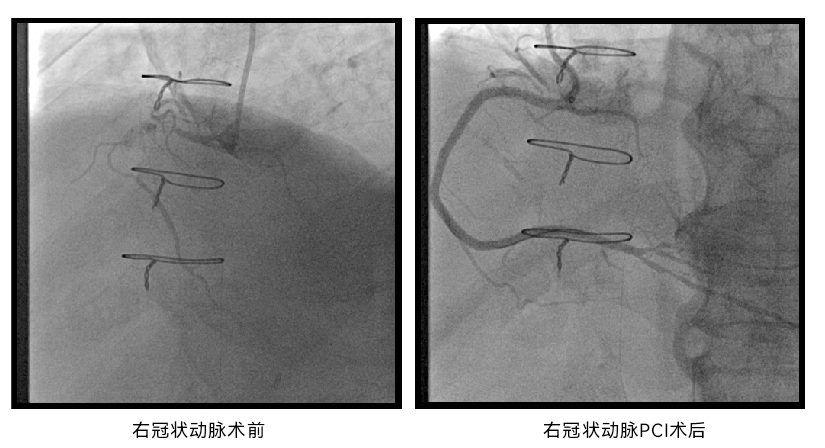

先由心内科团队完成右冠脉慢性完全闭塞(CTO)病变介入治疗,植入支架,改善冠脉供血,为后续治疗提供保障;再用经导管方式置换主动脉瓣(TAVR),由心外科与血管外科通过局部切开后穿刺股动脉,球囊扩张狭窄的髂动脉后建立了TAVR入路,心内科团队完成植入26mm球囊扩张式瓣膜;最后由血管外科团队完成髂动脉支架植入,同台解决其髂动脉狭窄问题。